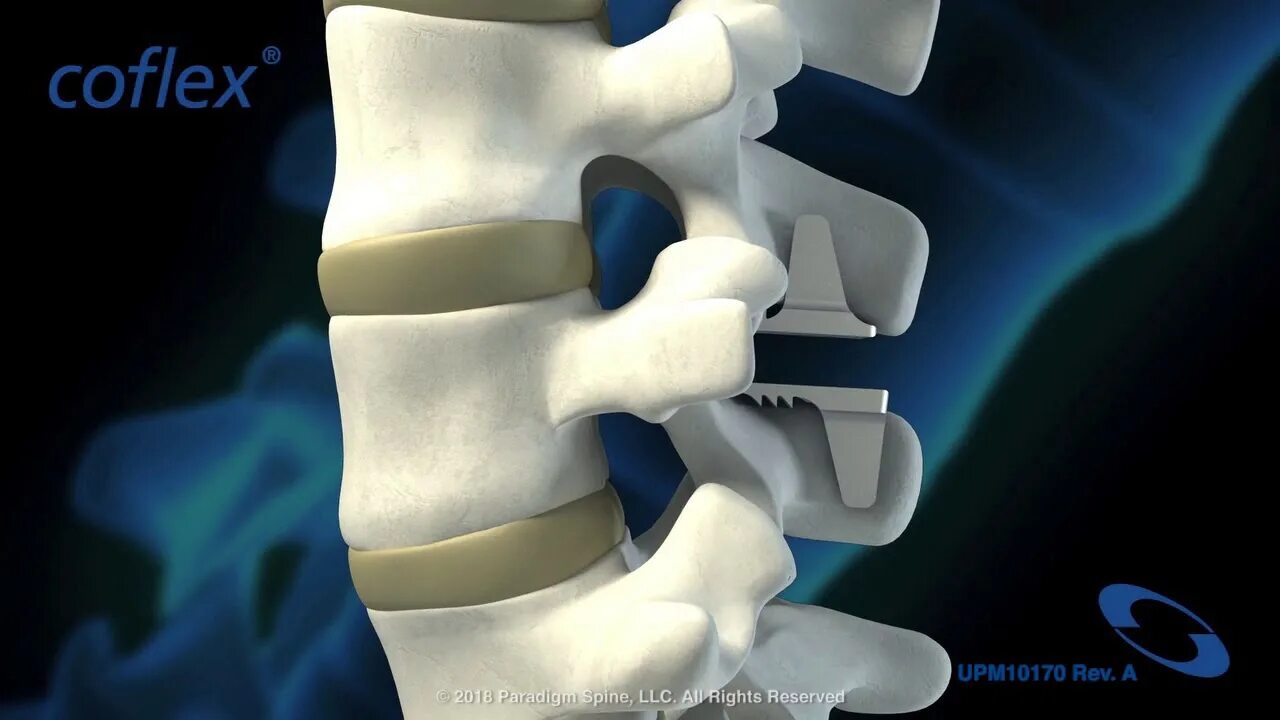

Установка кейджа в позвоночнике